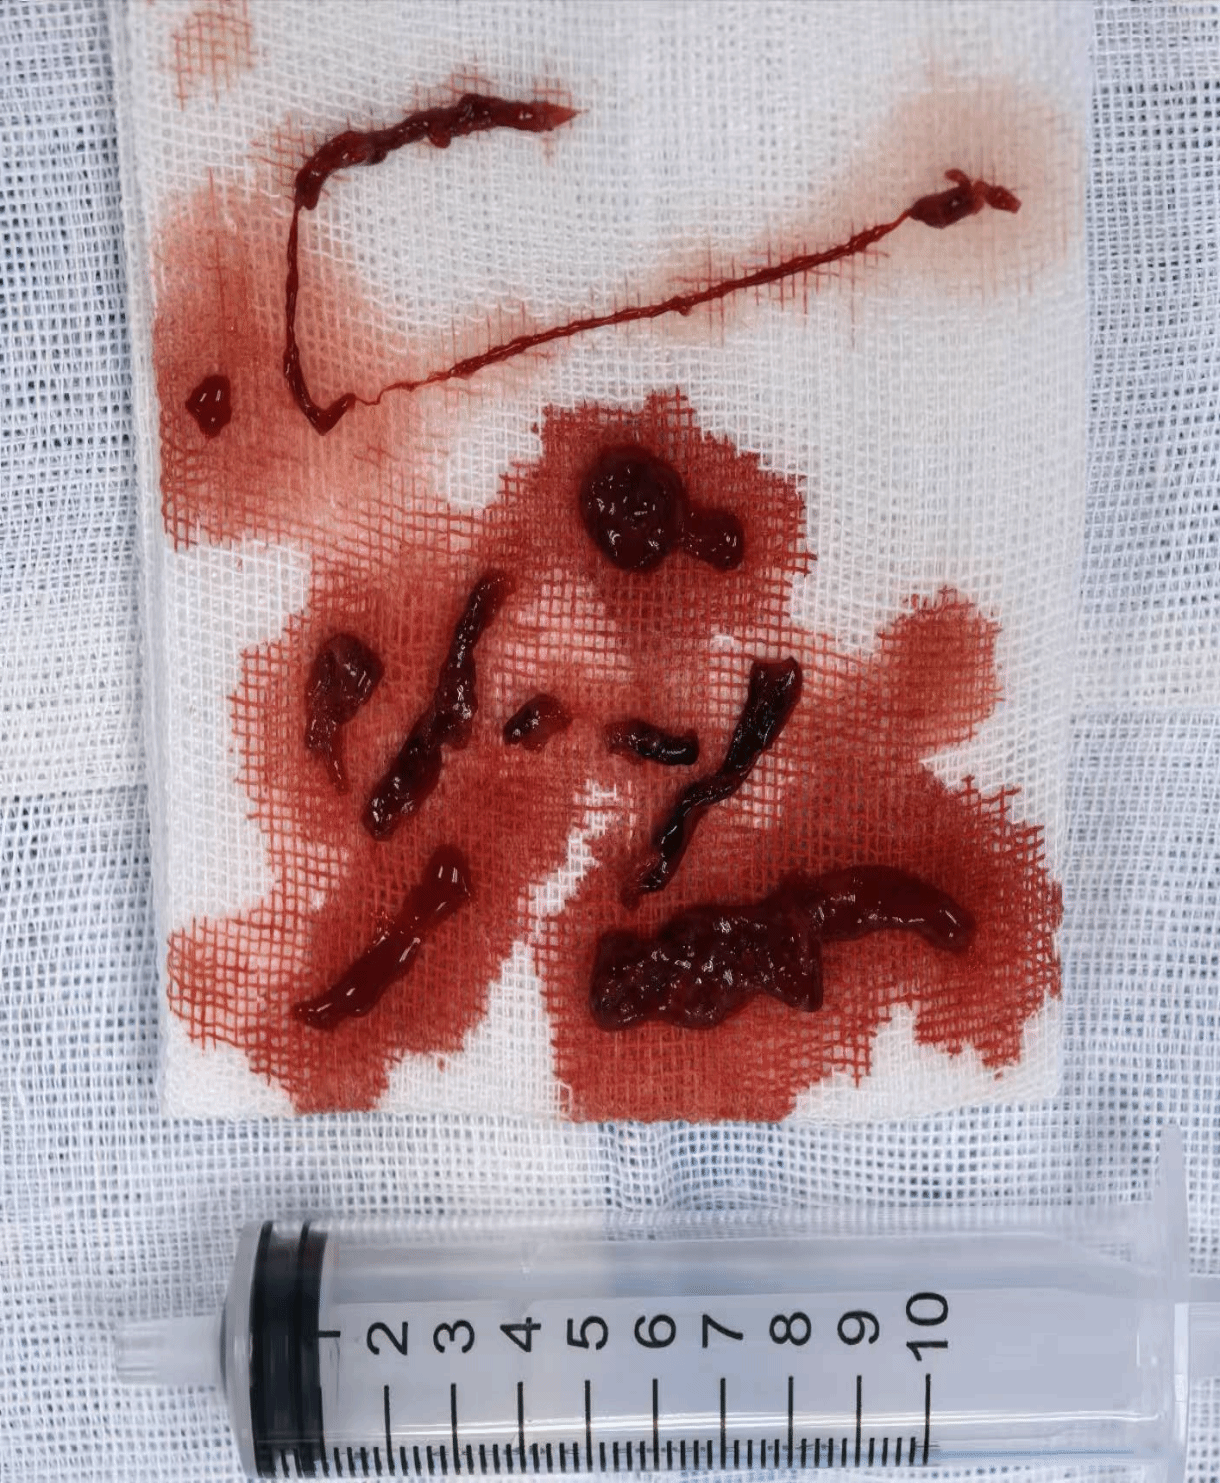

动脉取出的血栓